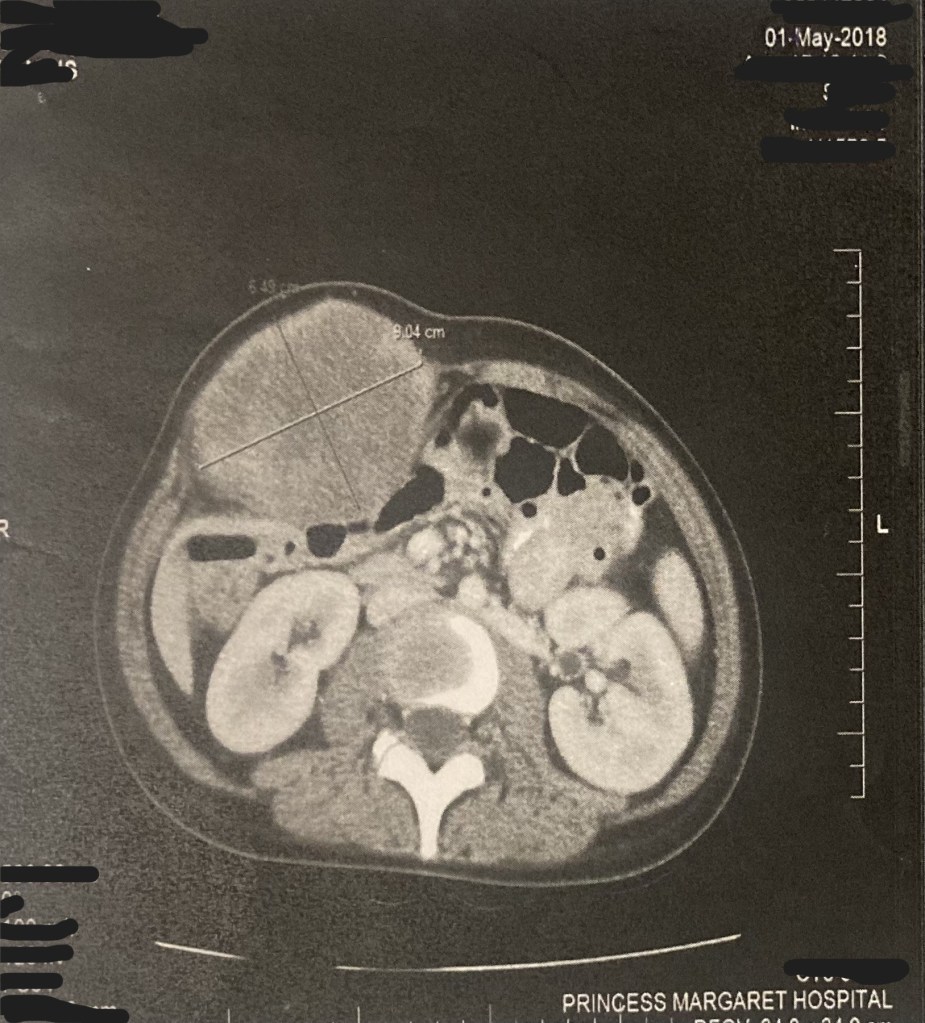

Sure, a small, normal, every day tumor.

Everyone’s been asked if they were pregnant because of a tumor once.